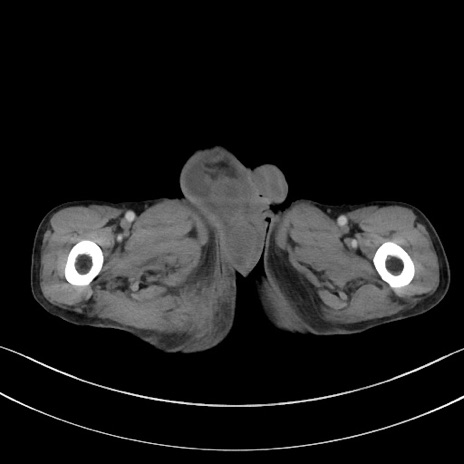

症例3(横断像)

症例

【症例】 70歳代男性

【主訴】右鼠径部腫瘤、疼痛

【現病歴】本日朝より上記主訴あり、受診。

【既往歴】膀胱癌にて膀胱全摘、両側尿管皮膚瘻

【データ】WBC 5600、CRP 0.56